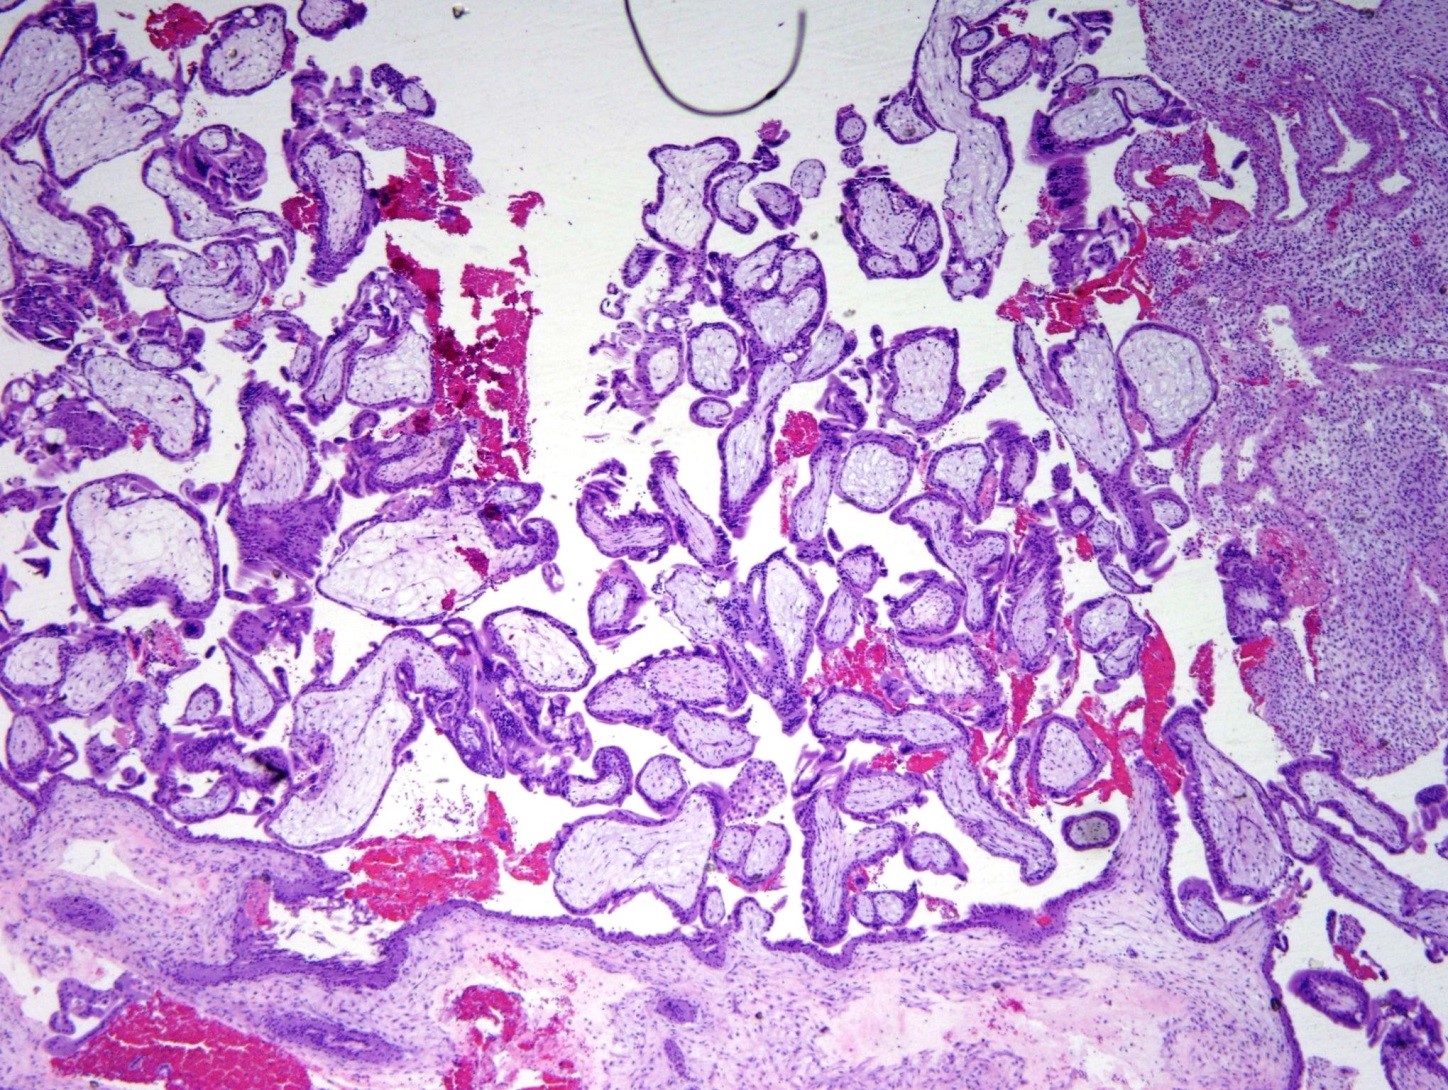

- Villi are small (size of 2-2.5 endometrial glands or <4 mm) (figure 1).

- Trophoblastic proliferation in polarized (trophoblasts grow in columns towards the oxygen source)